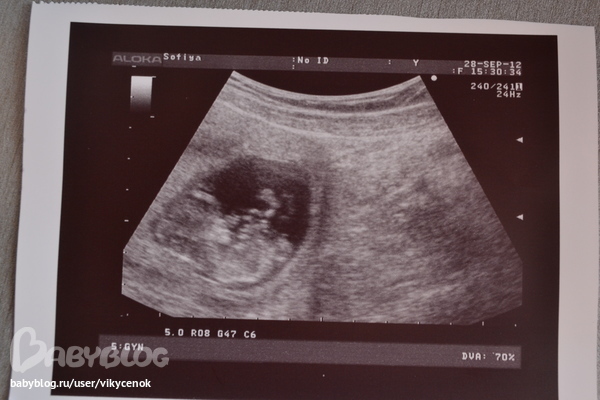

еще одно наше узи...

Вопросы про УЗИ, обследования и анализы: что, где, как, когда?после отравления врач сразу направила на узи..не мешкая,посмотреть как там поживает мой лялик=) вот что нам написала врач...

срок 11 неделек,

КТР 41мм,БПР 17мм.

Сердцебиение 152ЧСС

толщина воротникового пространства 1,6мм

длина костей носа 3,2 мм

Амнион 52мм

Хориальная полость 15мм

локализачия ворсинчатого хориона: передняя!